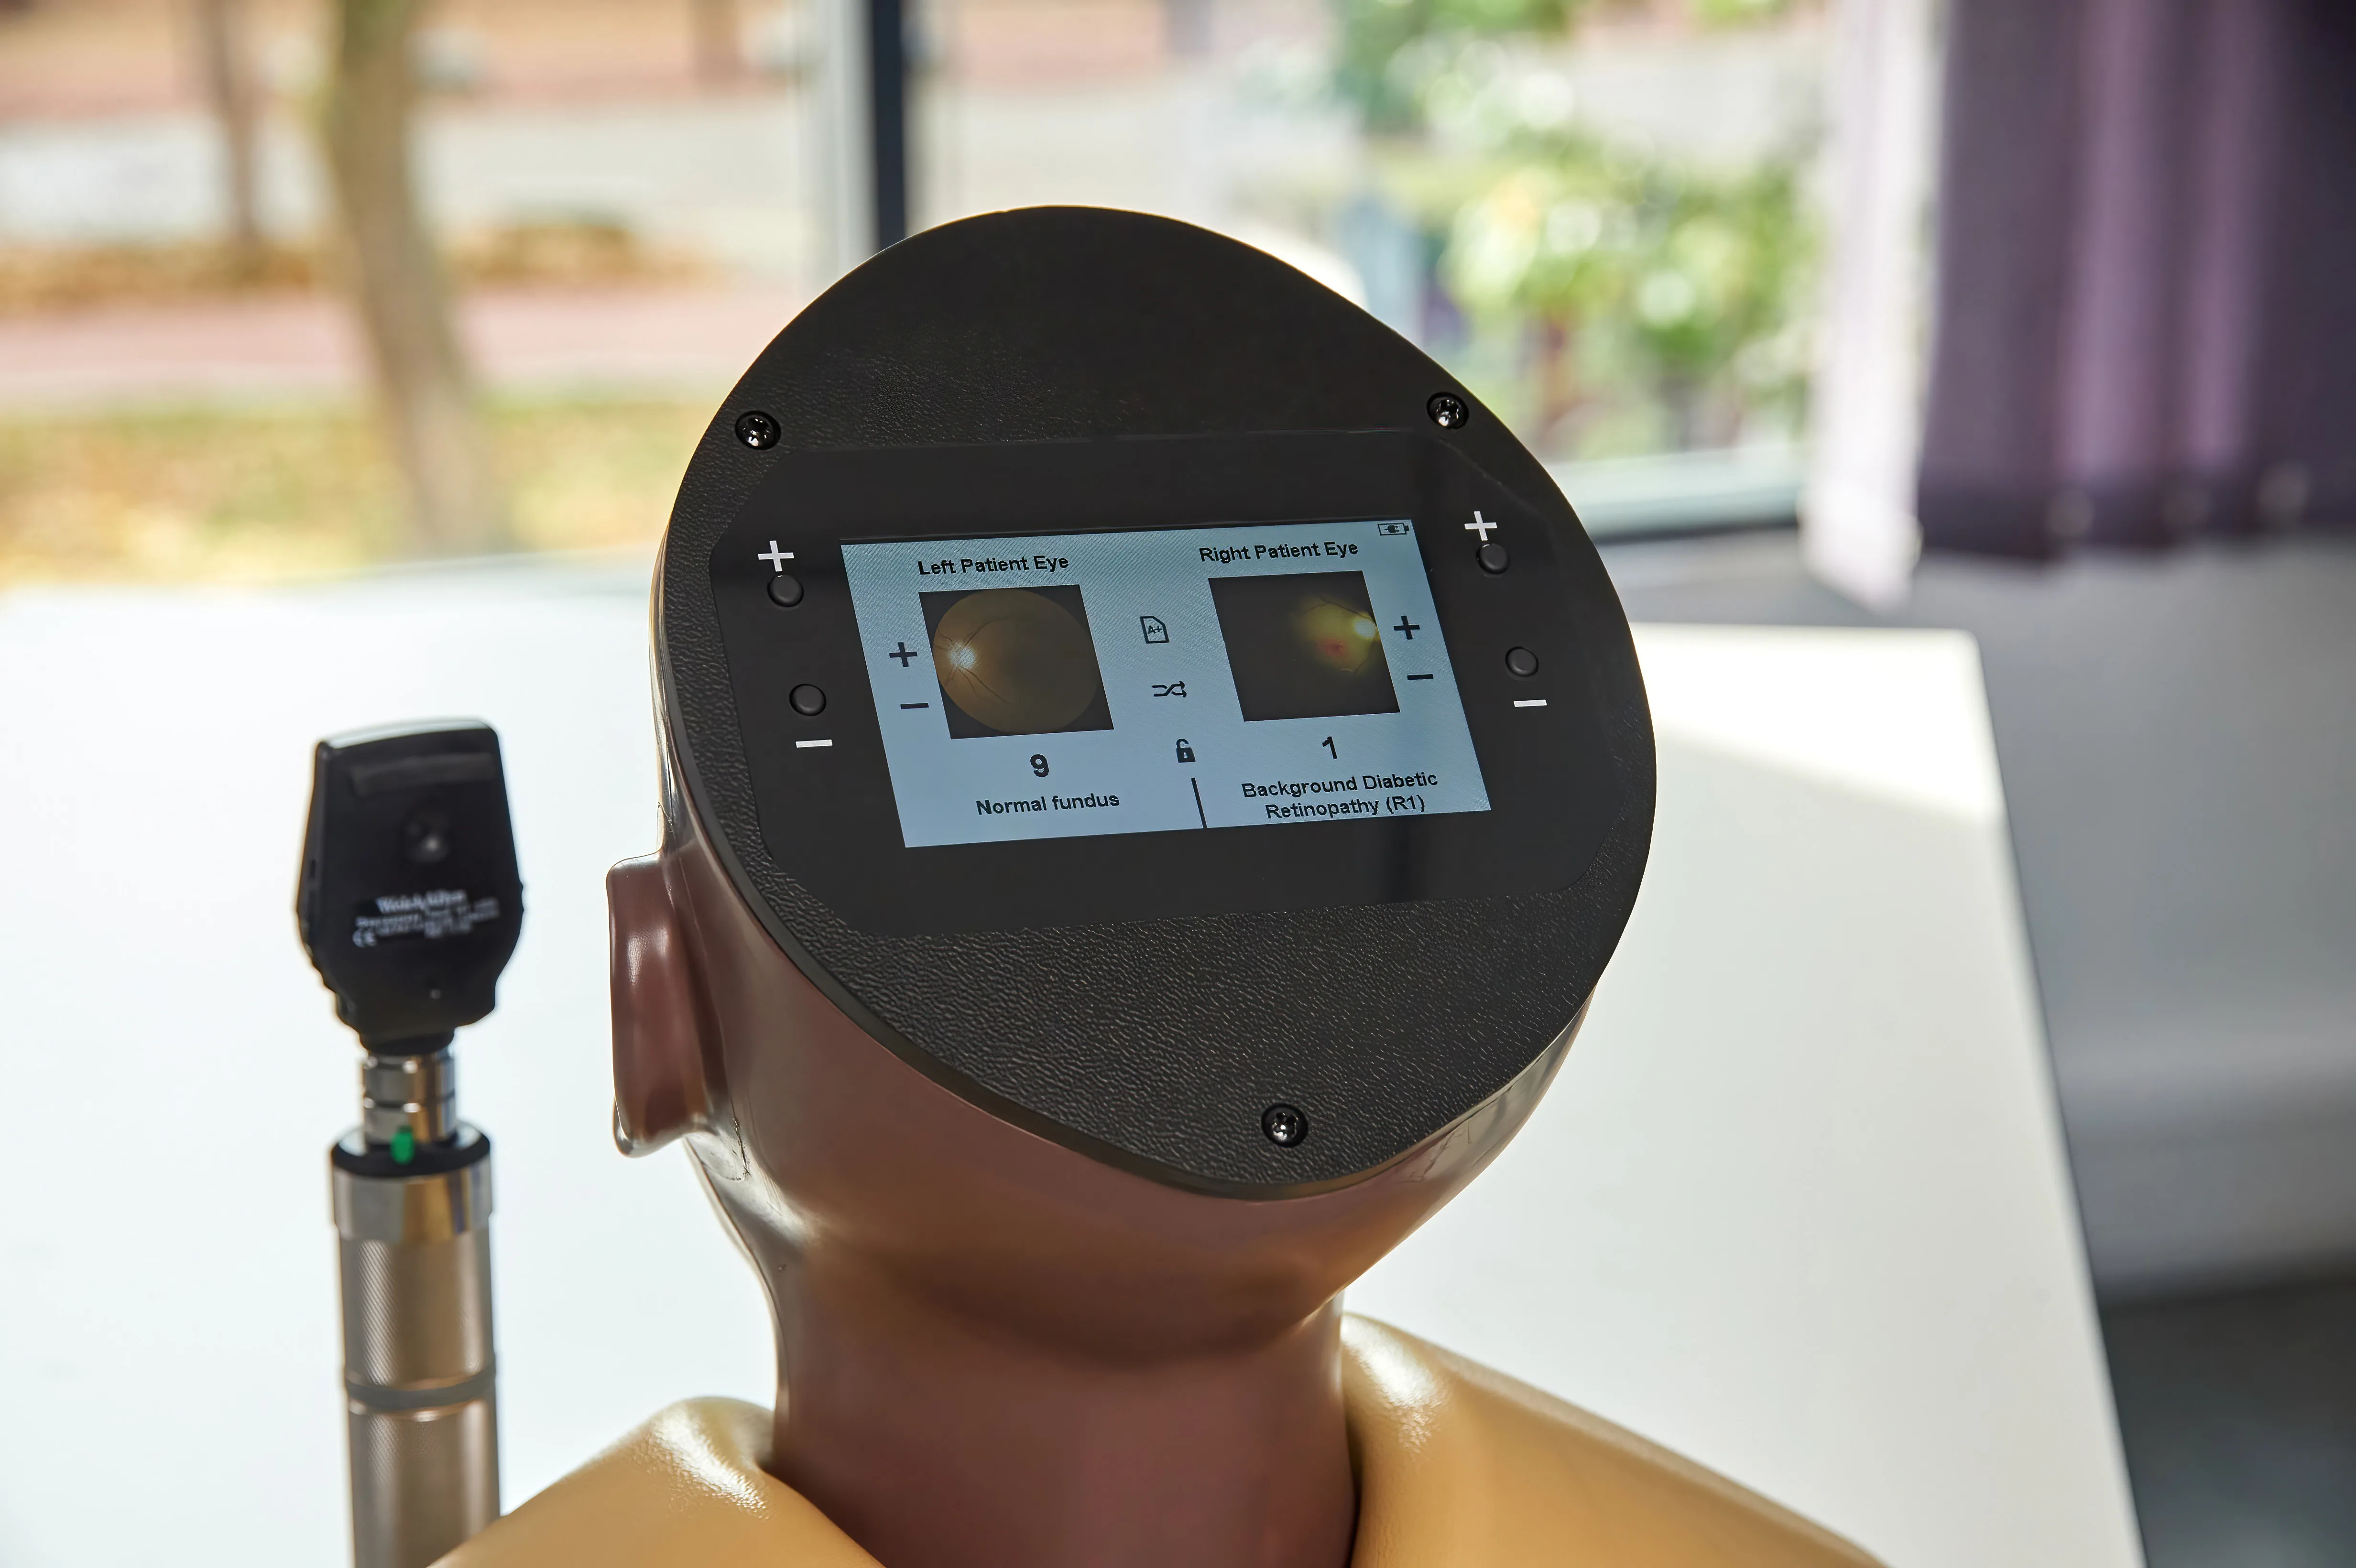

Inside the model, conditions are displayed with greater clarity and true-to-life colour on high-resolution circular LCD screens. A 4.3-inch external touchscreen interface makes operation intuitive and effective, allowing users to preview, search, and select conditions or build customisable sets for teaching, self-directed learning, or examination scenarios.

Condition Library: browse names and image previews for all 36 eye conditions

Search Function: instantly locate a condition for teaching or self-directed study

Random Mode: display conditions in a varied sequence to keep learners interested

Custom Sets: select up to 10 specific conditions in any order, for focused teaching or assessments

Exam Mode: hide condition names and numbers for authentic test conditions. Sleep Mode is automatically disabled for uninterrupted practice

Lock Mode – displays the last selected condition for both left and right patient eyes

Eye conditions and diseases presented digitally for the light skin toned patients AR503 and dark skin toned patients AR503/50:

Diabetic Retinopathy:

Background Diabetic Retinopathy (R1) with Maculopathy (M0)